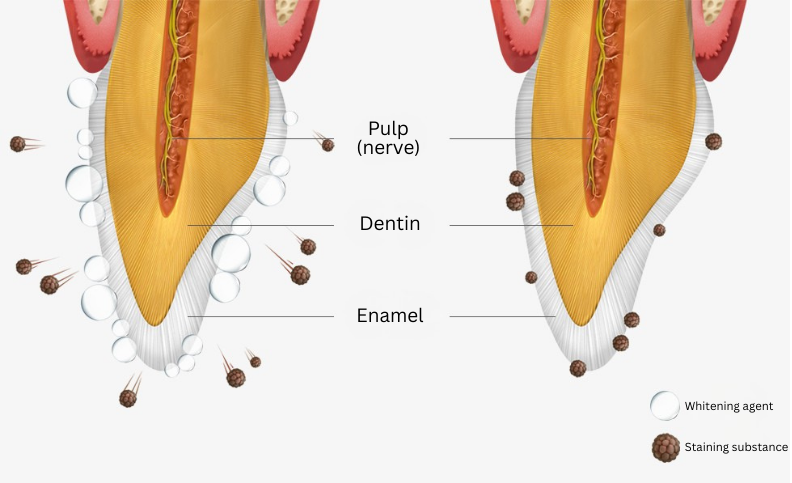

How Does Vital Whitening Work?

The whitening effect occurs by using hydrogen peroxide as a whitening agent to break down the molecular structure of stains inside the teeth, resulting in a whitening effect.

In-Office Vital Whitening Process

In-Office whitening involves the direct application of highly concentrated bleaching agents onto the teeth after ensuring the gums and mouth are properly protected. This method is known for delivering significant whitening results, making it a popular choice for those seeking immediate improvements in the brightness of their smile. The process is safe, effective, and monitored by medical staff to ensure the health and safety of the patient’s teeth and gums throughout the procedure.